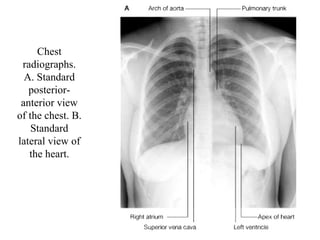

Chest radiographs. A. Standard posterior-anterior view of the chest. B. Standard lateral view of the heart.

Chest radiographs. A.Standard posterior-anterior view of the chest. B. Standard lateral view of the heart.